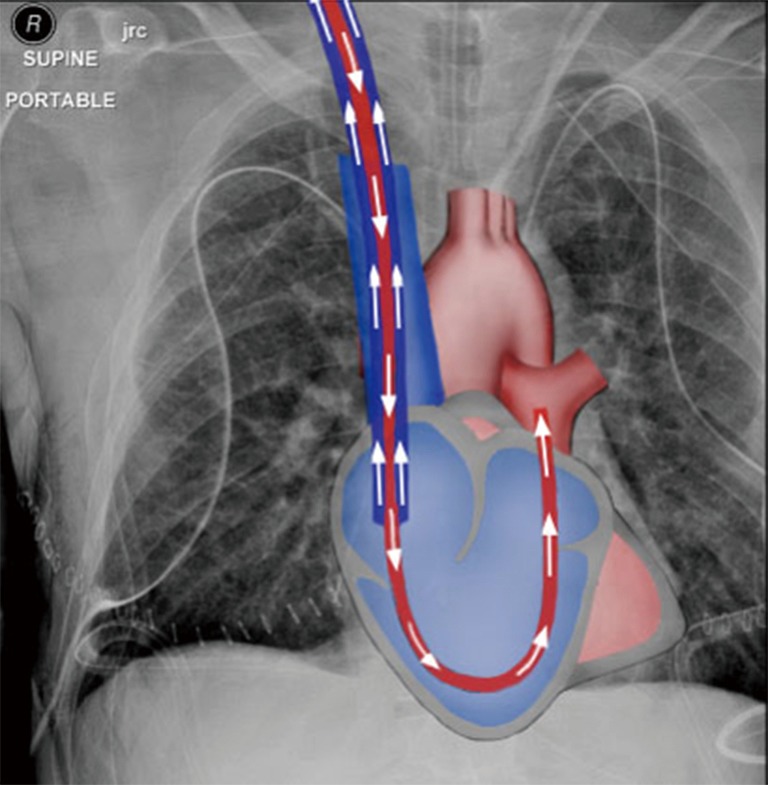

We reasoned that RV bypass combined with extracorporeal membrane oxygenation, using a percutaneous approach, would be sufficient to address the most common indications for cardiopulmonary support during lung transplantation, namely poor gas exchange and RV support, while obviating the inherent risks of CPB and VA-ECMO. We explored the merits of the two percutaneous devices available for RV support, the ProtekDuo (CardiacAssist, Inc., Pittsburgh, PA, USA) dual-lumen cannula (DLC) and the Impella RP (Abiomed, Inc., Danvers, MA, USA), and selected the former since it can be connected to an ECMO circuit. When used in a right atrial-pulmonary artery configuration (Figure 1), deoxygenated blood is drained from the right atrium and oxygenated blood is returned into the main pulmonary artery (PA), bypassing and unloading the RV.

Right atrial-pulmonary artery configuration of a dual lumen cannula drawing deoxygenated blood from the right atrium and returning oxygenated blood into the main PA, bypassing the RV. PA, pulmonary artery; RV, right ventricle.